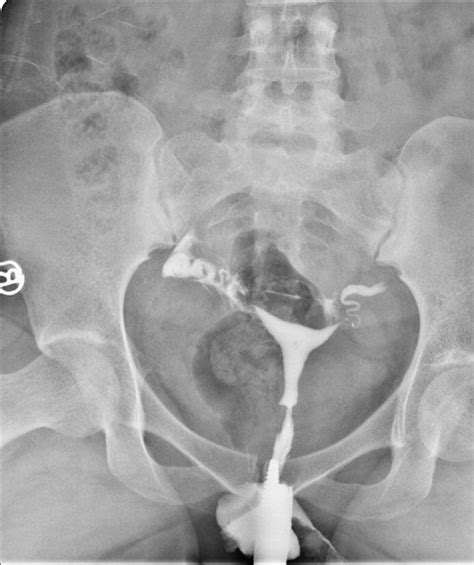

| Histerosalpingografija (HSG) | Rentgeno tyrimas su kontrastine medžiaga | Nustatyti kiaušintakių pralaidumą |